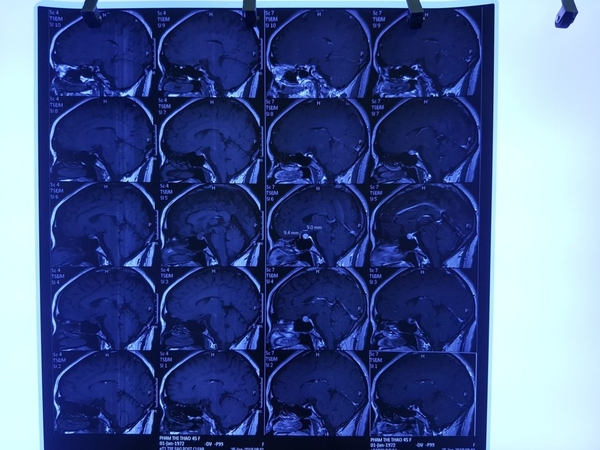

Diễn biến bệnh: Cuối năm 2017 bệnh nhân thấy đau đầu nhiều, chóng mặt, nôn và buồn nôn, không ăn được, mệt mỏi nhiều. Bệnh nhân đi khám và chỉ định chụp MRI sọ não tại Thanh Hóa phát hiện U tuyến yên.

Tháng 1/2018 BN ra BV TW Quân Đội 108 khám lại được chẩn đoán U tuyến yên kích thước lớn, gây hiệu ứng khối choán chỗ. BN được cho nhập viện và chỉ định mổ nội soi nhưng xin về điều trị nội khoa trước. BN được uống KILCEL 500mg 3 tháng, sau uống KILCEL thấy hết đau đầu, hết chóng mặt, hết nôn buồn nôn, ăn uống trở lại bình thường, không còn mệt mỏi.

Tháng 4/2018 chụp MRI sọ não sau uống KILCEL 3 tháng thấy khối U tuyến yên teo nhỏ.

Kết quả trước uống KILCEL 500mg